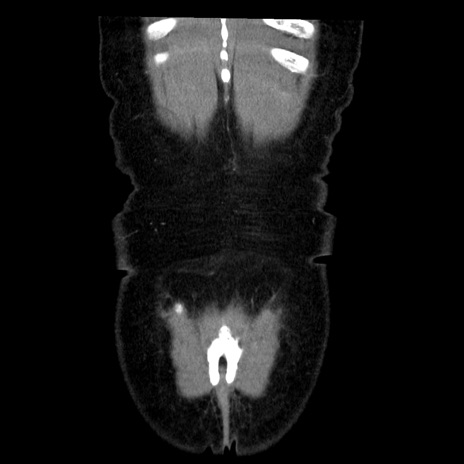

横断像

矢状断像